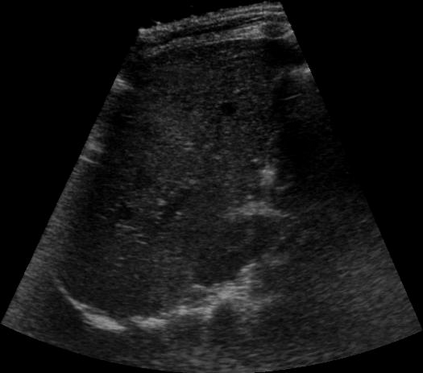

Most deep neural networks (DNNs) based ultrasound (US) medical image analysis models use pretrained backbones (e.g., ImageNet) for better model generalization. However, the domain gap between natural and medical images causes an inevitable performance bottleneck. To alleviate this problem, an US dataset named US-4 is constructed for direct pretraining on the same domain. It contains over 23,000 images from four US video sub-datasets. To learn robust features from US-4, we propose an US semi-supervised contrastive learning method, named USCL, for pretraining. In order to avoid high similarities between negative pairs as well as mine abundant visual features from limited US videos, USCL adopts a sample pair generation method to enrich the feature involved in a single step of contrastive optimization. Extensive experiments on several downstream tasks show the superiority of USCL pretraining against ImageNet pretraining and other state-of-the-art (SOTA) pretraining approaches. In particular, USCL pretrained backbone achieves fine-tuning accuracy of over 94% on POCUS dataset, which is 10% higher than 84% of the ImageNet pretrained model. The source codes of this work are available at https://github.com/983632847/USCL.